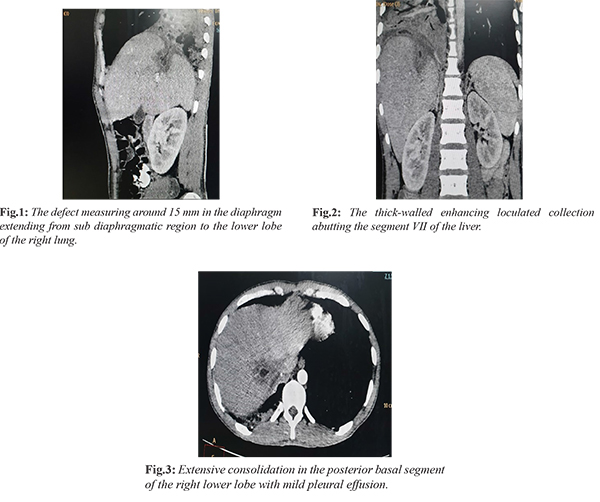

During the course of hospitalization, the patient developed right-sided pleuritic chest pain with productive foul-smelling green colored, copious, mucoid sputum occasionally blood-stained. Sputum was sent for the culture sensitivity which revealed no significant bacterial growth. Suspecting pleuro-pulmonary complication of hepatic abscess, computed tomography imaging of chest with abdomen was done. CT scan was suggestive of extensive consolidation in the posterior basal segment of the right lower lobe with mild pleural effusion which was extending to the sub-diaphragmatic region through the defect measuring 15 mm in the diaphragm and forming the thick-walled enhancing loculated collection abutting the segment VII of the liver [Fig.1-3].